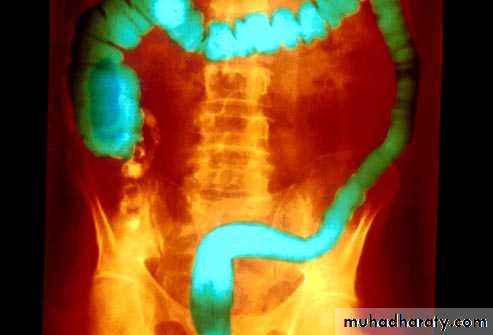

Chronic stage

o Shortening of the colon-may be from spasm of longitudinal muscles or from irreversible fibrosis (lead-pipe colon)

o Loss of haustrations on left side of colon

Barium enema examination demonstrates loss of haustral folds in the entire descendingcolon with small ulcerations suggested. The colon has a "lead-pipe" appearance. The distribution and appearance are suggestive of ulcerative colitis.